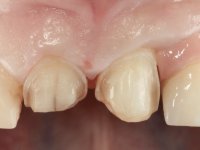

Female patient, 47 years old non-smoker. Tooth 1.3 with endodontic treatment and a cast post and core, rehabilitated with a provisional crown. The two upper lateral incisors are conoid and of small dimension. Tooth 2.2 presents mobility, in agreement with a significant bone reabsorption between teeth 2.1 and 2.3. The two central incisors are separated by a 3 mm diastema and tooth 2.3 presents a crossed occlusion with the opposing tooth. There is also an absence of some posterior teeth and reasonable oral hygiene. In the second intervention performed 8 years later, it was verified that the upper central incisors were chromatically darker and had a longitudinal groove in the enamel which, being pigmented, aesthetically compromised the smile. The work performed in the first phase of the treatment was competent, aesthetically and functionally. Finally, one year after the last intervention, the patient complained of a fracture on the veneer placed on tooth 2.1, probably as a result of being in contact with the abutment of the implant. The rigidity of implant ankylosis may have been the cause of this fracture. I have observed other instances of this type of fracture in identical clinical situations. The veneer of tooth 1.2 was aesthetically compromised and the dental structure itself had small caries and, therefore, its replacement would be recommended.

Eight years later, in the second intervention, the following treatment was proposed:

• Restoration of teeth Superior Central Incisors with feldspathic ceramic veneers.